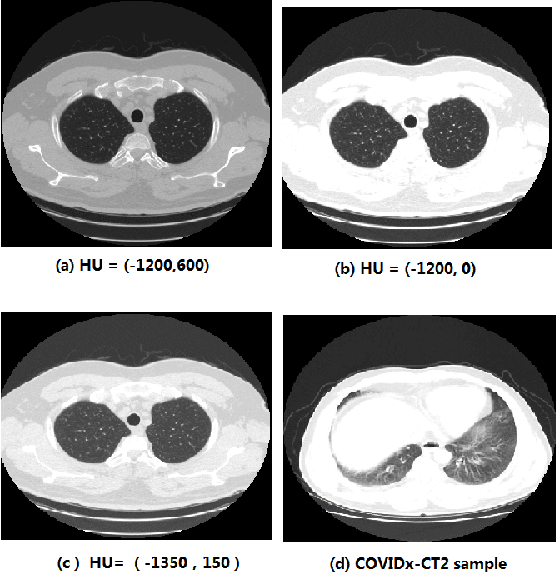

Abstract:We present an automatic COVID1-19 diagnosis framework from lung CT images. The focus is on signal processing and classification on small datasets with efforts putting into exploring data preparation and augmentation to improve the generalization capability of the 2D CNN classification models. We propose a unique and effective data augmentation method using multiple Hounsfield Unit (HU) normalization windows. In addition, the original slice image is cropped to exclude background, and a filter is applied to filter out closed-lung images. For the classification network, we choose to use 2D Densenet and Xception with the feature pyramid network (FPN). To further improve the classification accuracy, an ensemble of multiple CNN models and HU windows is used. On the training/validation dataset, we achieve a patient classification accuracy of 93.39%.